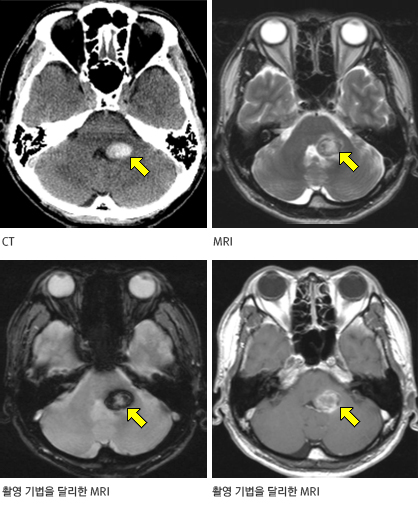

뇌혈관질환

뇌동맥류, 경동맥협착증, 모야모야병, 뇌혈관기형, 혈관박리, 뇌동맥 협착증